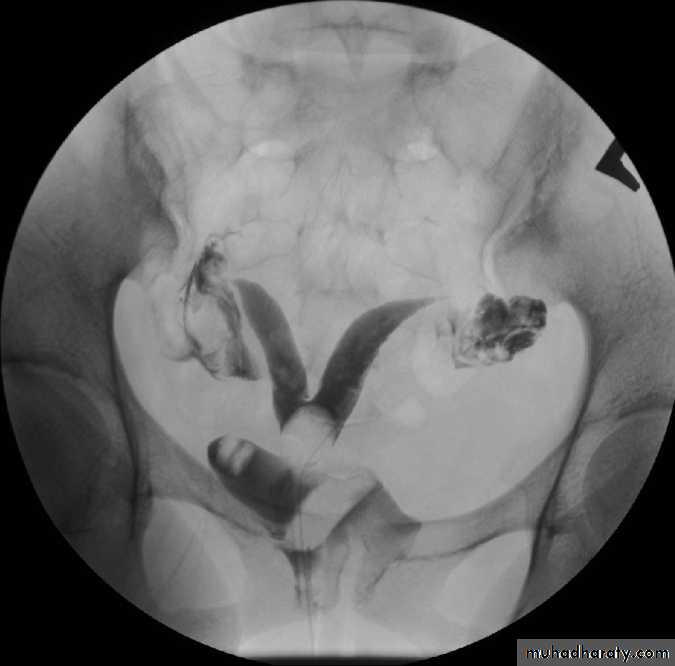

HSG : bicornuate uterus